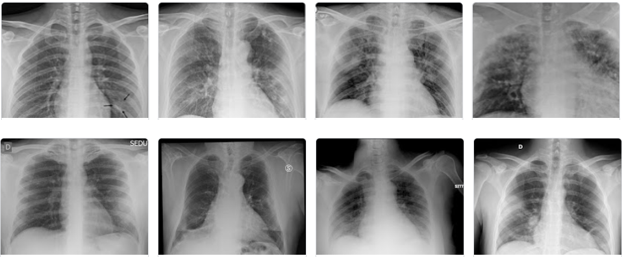

CLAHE algorithm overcomes the issue of global histogram equalization incurred due to noise amplification in homogeneous regions. It computes different histograms and utilizes them to redistribute the lightness value [15]. Primarily, CLAHE enhances the low-contrast medical images with the help of control image enhancement quality parameters, i.e., Block Size (BS) and Clip Limit (CL) [36]. CL limits the noise amplification by clipping histograms at a specified value before computing the Cumulative Distribution Function (CDF). Figure 1 and Figure 2 show non-aumgneted and augmented chest X-ray images.

Figure 2: CLAHE-enabled augmented chest X-ray images.